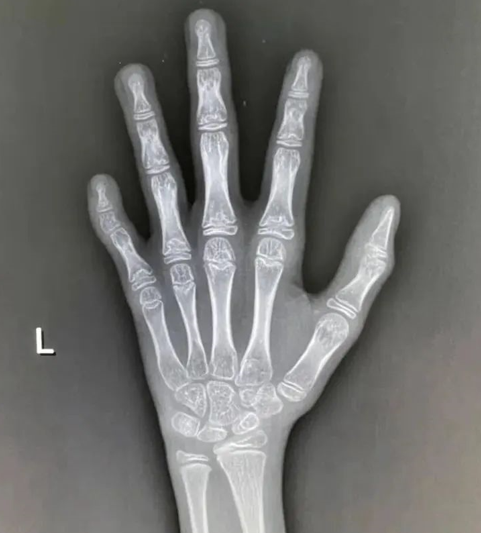

如果偏离了正常范围,测骨龄只需配合完成一次左侧腕关节正位X线光片拍摄即可。

拍完骨龄片后,医生一般会根据简单计数法、图谱法、评分法或者计算机骨龄评分系统等来评价(目前最常用的是G-P图谱法和TW3评分法)。